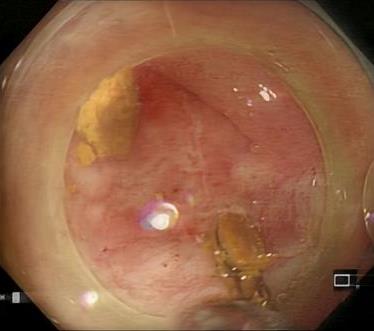

• 一次性子母胆道镜辅助内镜逆行阑尾炎治疗术对急性非复杂性阑尾炎的诊断和治疗价值分析

摘要:目的 探讨一次性子母胆道镜辅助内镜逆行阑尾炎治疗术在急性非复杂性阑尾炎治疗中的诊断和治疗价值。方法 回顾性分析2022年9月-2024年9月该院内镜中心通过一次性子母胆道镜辅助内镜逆行阑尾炎治疗术治疗的39例急性非复杂性阑尾炎患者的临床资料,观察内镜下表现、子母网篮取石率、阑尾支架置入率、技术成功率、临床成功率、手术时间、住院时间、并发症发生率和术后6 h视觉模拟评分法(VAS)评分,以及术后24 h炎症指标。结果 28例(71.8%)患者结肠镜下阑尾开口可见充血和水肿,10例(25.6%)患者结肠镜下阑尾开口可见脓液流出,32例(82.1%)患者子镜下阑尾腔内可见大量脓液,20例(51.3%)患者子镜下阑尾腔内可见粪石;一次性子母胆道镜辅助内镜逆行阑尾炎治疗术的技术成功率为100.0%(39/39);手术时间(21.08±7.49)min;住院时间(3.97±2.08)d;8例(20.5%)患者行内镜下子母网篮取石术;14例(35.9%)患者行阑尾支架置入术。临床成功率为97.4%(38/39),1例患者术后临床症状和炎症指标未缓解,转外科行阑尾切除术。38例患者术后6 h的VAS评分 < 3分,腹痛症状明显缓解;术后24 h白细胞计数和中性粒细胞百分比较术前明显下降,差异均有统计学意义(P < 0.05);39例患者均未发生并发症;术后随访(5.94±4.03)个月,3例(7.7%)出现复发。结论 一次性子母胆道镜辅助内镜逆行阑尾炎治疗术诊断和治疗急性非复杂性阑尾炎,安全且有效,值得临床推广应用。